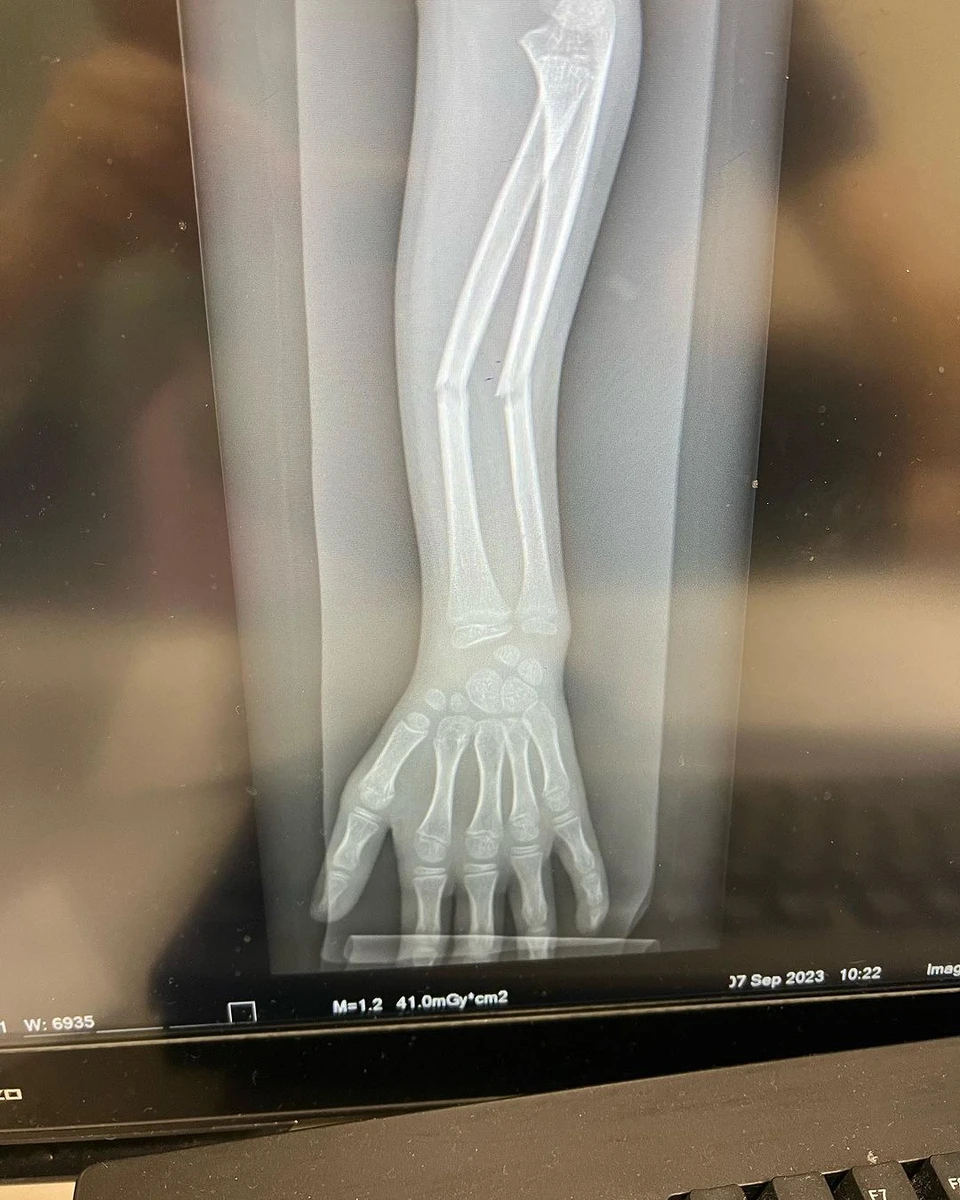

Вона опублікувала фото доньки та рентгенівські знімки, на яких добре видно, що перелом у дівчинки був серйозним.

Рентгенівський знімок перелому дівчинки